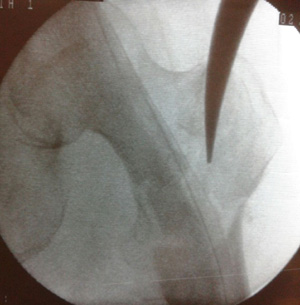

Figure 2a Radiograph showing lateralization and enlargement of the entry portal, with the nail acting as a distracting device (small arrow). Also note the varus mal-reduction (long arrow).

Figure 3b Preliminary fixation with K-wire before making entry point, so as to avoid loss of reduction while reaming and subsequent nail insertion.